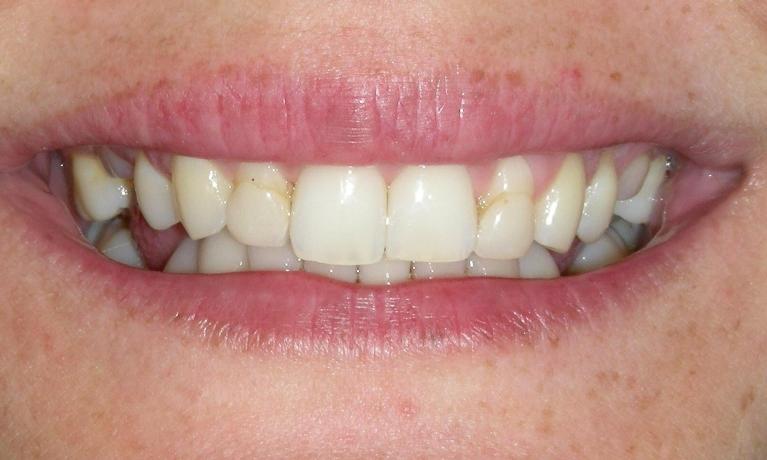

Before

Repair of fractured incisor with composite resin.

This young Yale student fractured her two front teeth a few days after arriving in New Haven to begin her graduate school. She had recently bleached her lower teeth before leaving home.

Composite resin was bonded to the fractured area, and her treatment was completed within an hour.